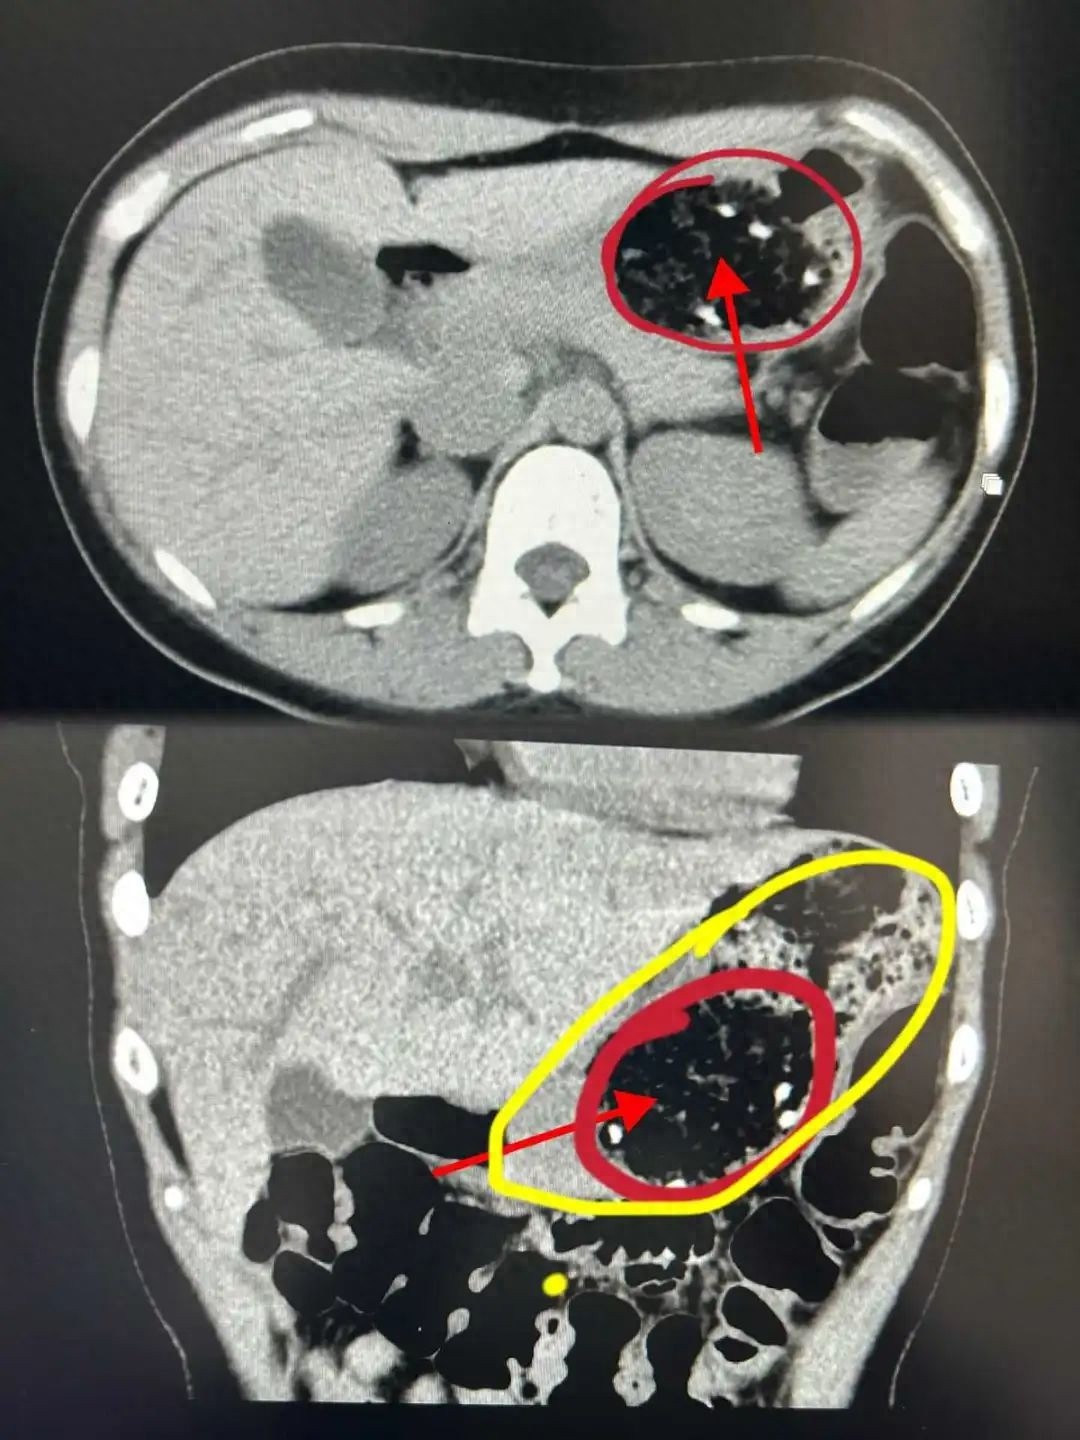

各地接连出现类似病例。以杭州47岁张先生为例,他在食用了山楂与板栗的混合食品后,不幸患上了直径5厘米、高8厘米的胃结石,不得不接受碎石手术。这一案例反映出健康问题的影响已相当广泛,公众需对此保持高度警觉。